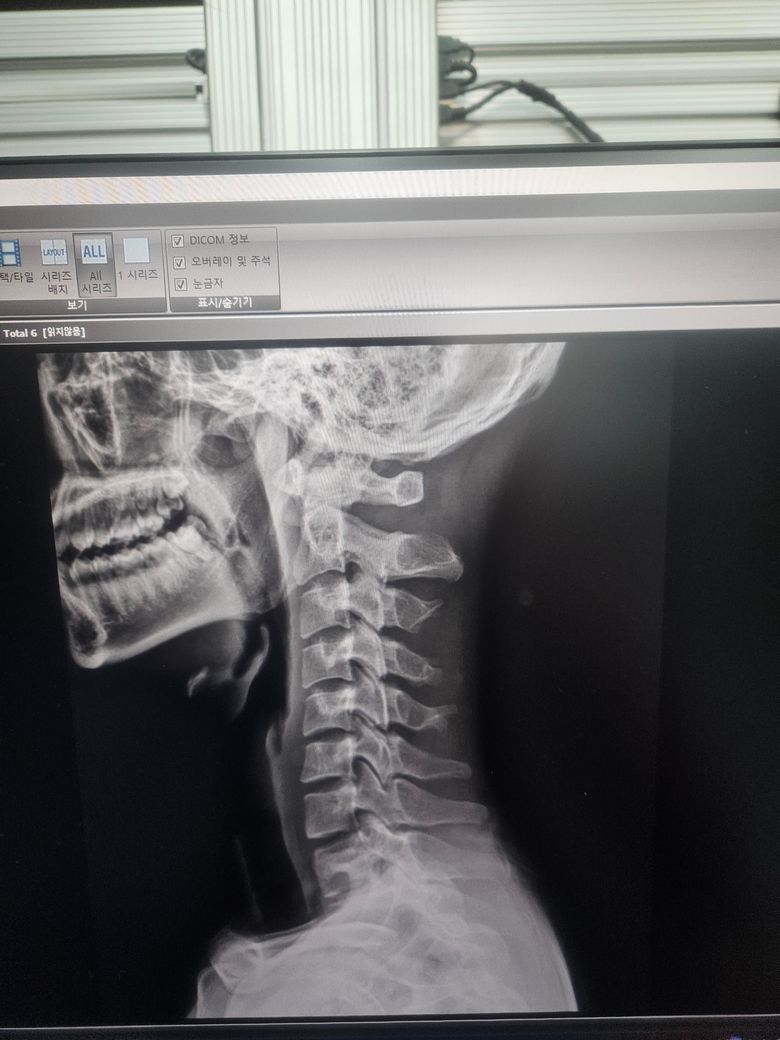

엑스레이상으로보이는건 목의 정상적인 C자커브가 줄어들고 일자목이되어있는 상태로 볼수있습니다 이럴경우 목의 정상적인 커브가 사라지기때문에 불안정성이나 불편감이 나타날수있고 주변 근육들의 긴장감을 유발할수있습니다 장기적으로볼때 두통이나 다른 관절염과같은문제들이 나타날수있으니 병원에서 검사를받아보시고 불편감이 있다면 도수치료등을 받으면서 관리하는것이 도움이될수있습니다

불안증은 잘 모르겠지만, 경추 1번이 후두골과 많이 가까워져있습니다. 그럼 후두하근이라는 근육이 지속적으로 압박을 받는다는 것을 의미하며, 그 부분이 압박을 받으면 두통이나 어지러움, 구토 증상이 나타날 수 있습니다. 지금 엑스레이 상 보면 경추 상단 부분 (1,2,3) 에 움직임이 유연하지 못해 보이며, 특히 경추1번이 후두골과 아주 인접하게 붙어있어 그런 증상이 나오는 것으로 보입니다. 이런 부분은 대체의학적 접근 방법으로 도수치료를 통해서 어느정도 해결할 수 있을거 같습니다. 아마 저정도로 목뼈가 뻣뻣하면 어깨 근육이나 척추도 뻣뻣할 것으로 예상됩니다. 도수치료나 운동치료 추천드립니다. 부디 잘 회복되시길 바라겠습니다. 감사합니다.

병명은 잘 모르겠으나 하부 경추에는 목의 커브가 조금 있는 방면에 상부에는 목의 커브가 없으신걸로 보입니다. 이로인해 경추의 하부에 불안정감과 압력이 더 생길 것으로 사료되머 경추 상부의 근육에 과도한 긴장과 이로인해 두통이 생길 수 있습니다. 따라서 평소 후두하근과 흉쇄유돌근을 스트레칭 및 마사지를 해주시고 평소 등 쪽 운동을 해주시면 도움이 되겠습니다.